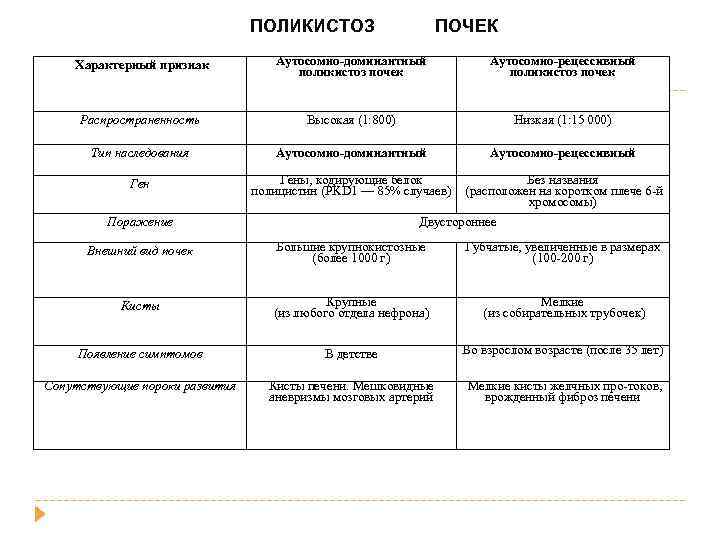

ПОЛИКИСТОЗ ПОЧЕК Характерный признак Аутосомно-доминантный поликистоз почек Аутосомно-рецессивный поликистоз почек Распространенность Высокая (1: 800) Низкая (1: 15 000) Тип наследования Аутосомно-доминантный Аутосомно-рецессивный Гены, кодирующие белок полицистин (PKD 1 — 85% случаев) Без названия (расположен на коротком плече 6 й хромосомы) Поражение Двустороннее Внешний вид почек Большие крупнокистозные (более 1000 г) Губчатые, увеличенные в размерах (100 200 г) Кисты Крупные (из любого отдела нефрона) Мелкие (из собирательных трубочек) Появление симптомов В детстве Во взрослом возрасте (после 35 лет) Сопутствующие пороки развития Кисты печени. Мешковидные аневризмы мозговых артерий Мелкие кисты желчных про токов, врожденный фиброз печени